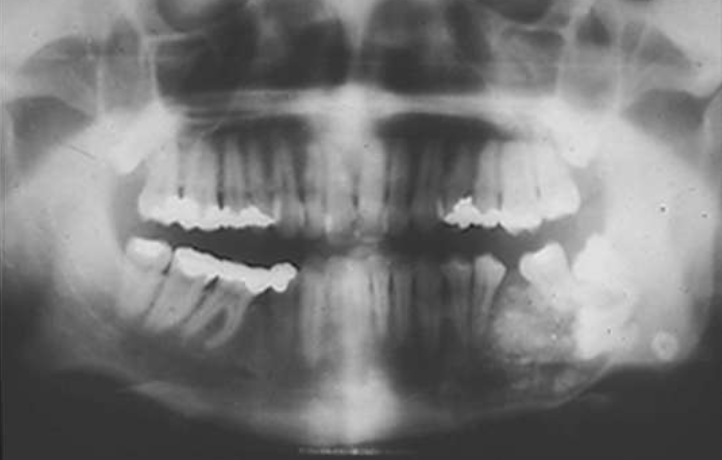

describe the ameloblastoma in this radiograph

multilocular w/ coarse septae

thinning of inferior mand border

displacement of teeth + IAN

T/F: you can see B/L expansion in this radiograph

false, since this PAN is a superimposed image- you cannot tell